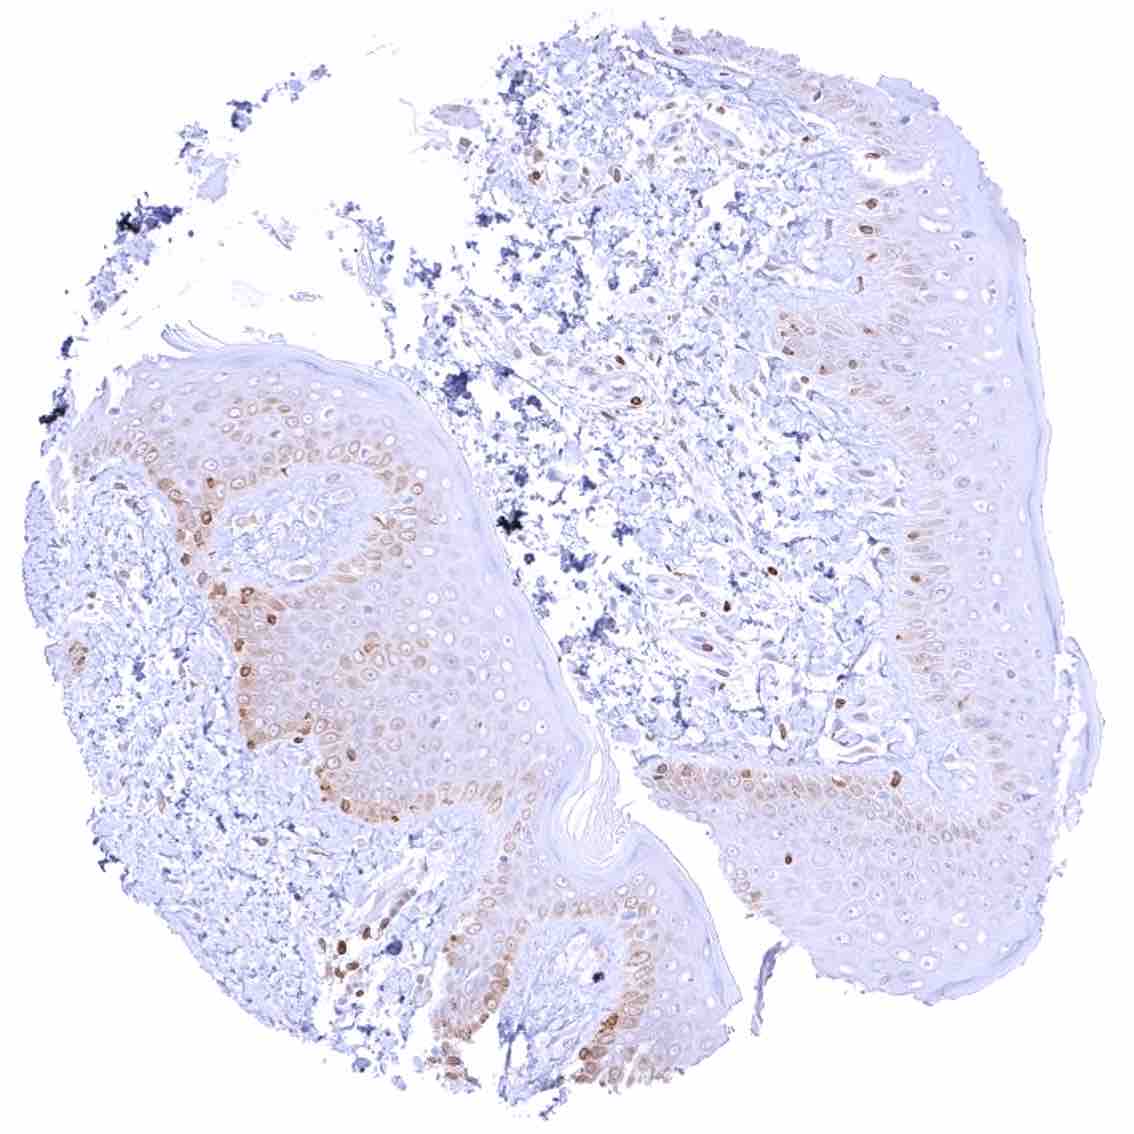

Tonsil –Strong bcl-2 positivity of large fraction of lymphocytic cells in the interfollicular area & around germinal centres. Cells in germinal centres are largely bcl-2 negative. Squamous epithelium with weak bcl-2 staining of the basal cell layer

Tonsil, surface epithelium